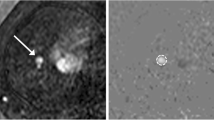

4D flow MRI provided datasets in 12/16 (75%) fetuses for flow quantification in all four target regions AAo, DAo, MPA, and DA. Time-velocity curves revealed typical arterial blood flow patterns with strong early systolic peaks and low positive diastolic blood velocities in the aorta (Fig. 3).

Example of time-velocity curves of the ascending aorta in a healthy fetus (A, dashed line) and a fetus with atrial septal defect (B, black line) but without any vascular pathology. Both fetuses had similar gestational age (37+4 and 37+1 weeks), heart rate (138 and 135 bpm), and cardiac cycle length (435 and 444 ms). The acquired temporal resolution was higher for fetus B (27 ms, interpolated to 24 cardiac phases) compared to fetus A (50 ms, interpolated to 13 cardiac phases) according to the modified scan protocols. Systolic peaks were lower for fetus A, potentially reflecting the lower temporal resolution and thus lower sensitivity to detect the systolic peak velocity